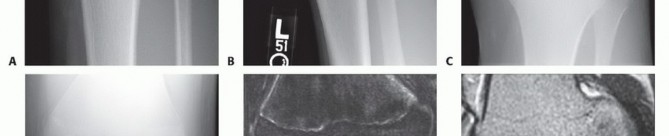

In OCD, plain films help to localize and characterize the lesion while also providing valuable information regarding skeletal maturity and age of the lesion and ruling out other bony injuries.

Radiographic evaluation should include anteroposterior (AP), lateral, tunnel, and sunrise views (

FIG 6A,B

).

Tunnel views provide visualization of the femoral condyles in greater profile than can be obtained with AP views (

FIG 6C,D

). The tunnel view often is the most revealing view because OCD lesions commonly are located on the lateral aspect of the medial femoral condyle.

FIG 6 • A,B. AP and lateral views demonstrating a lesion in the medial femoral condyle. C,D. AP and tunnel views demonstrating an OCD lesion of the lateral femoral condyle. The femoral condyles are in greater profile in the tunnel view, making the lesion easier to appreciate. E,F. Coronal and sagittal MRI images of an OCD lesion. Note the joint fluid present beneath the lesion.